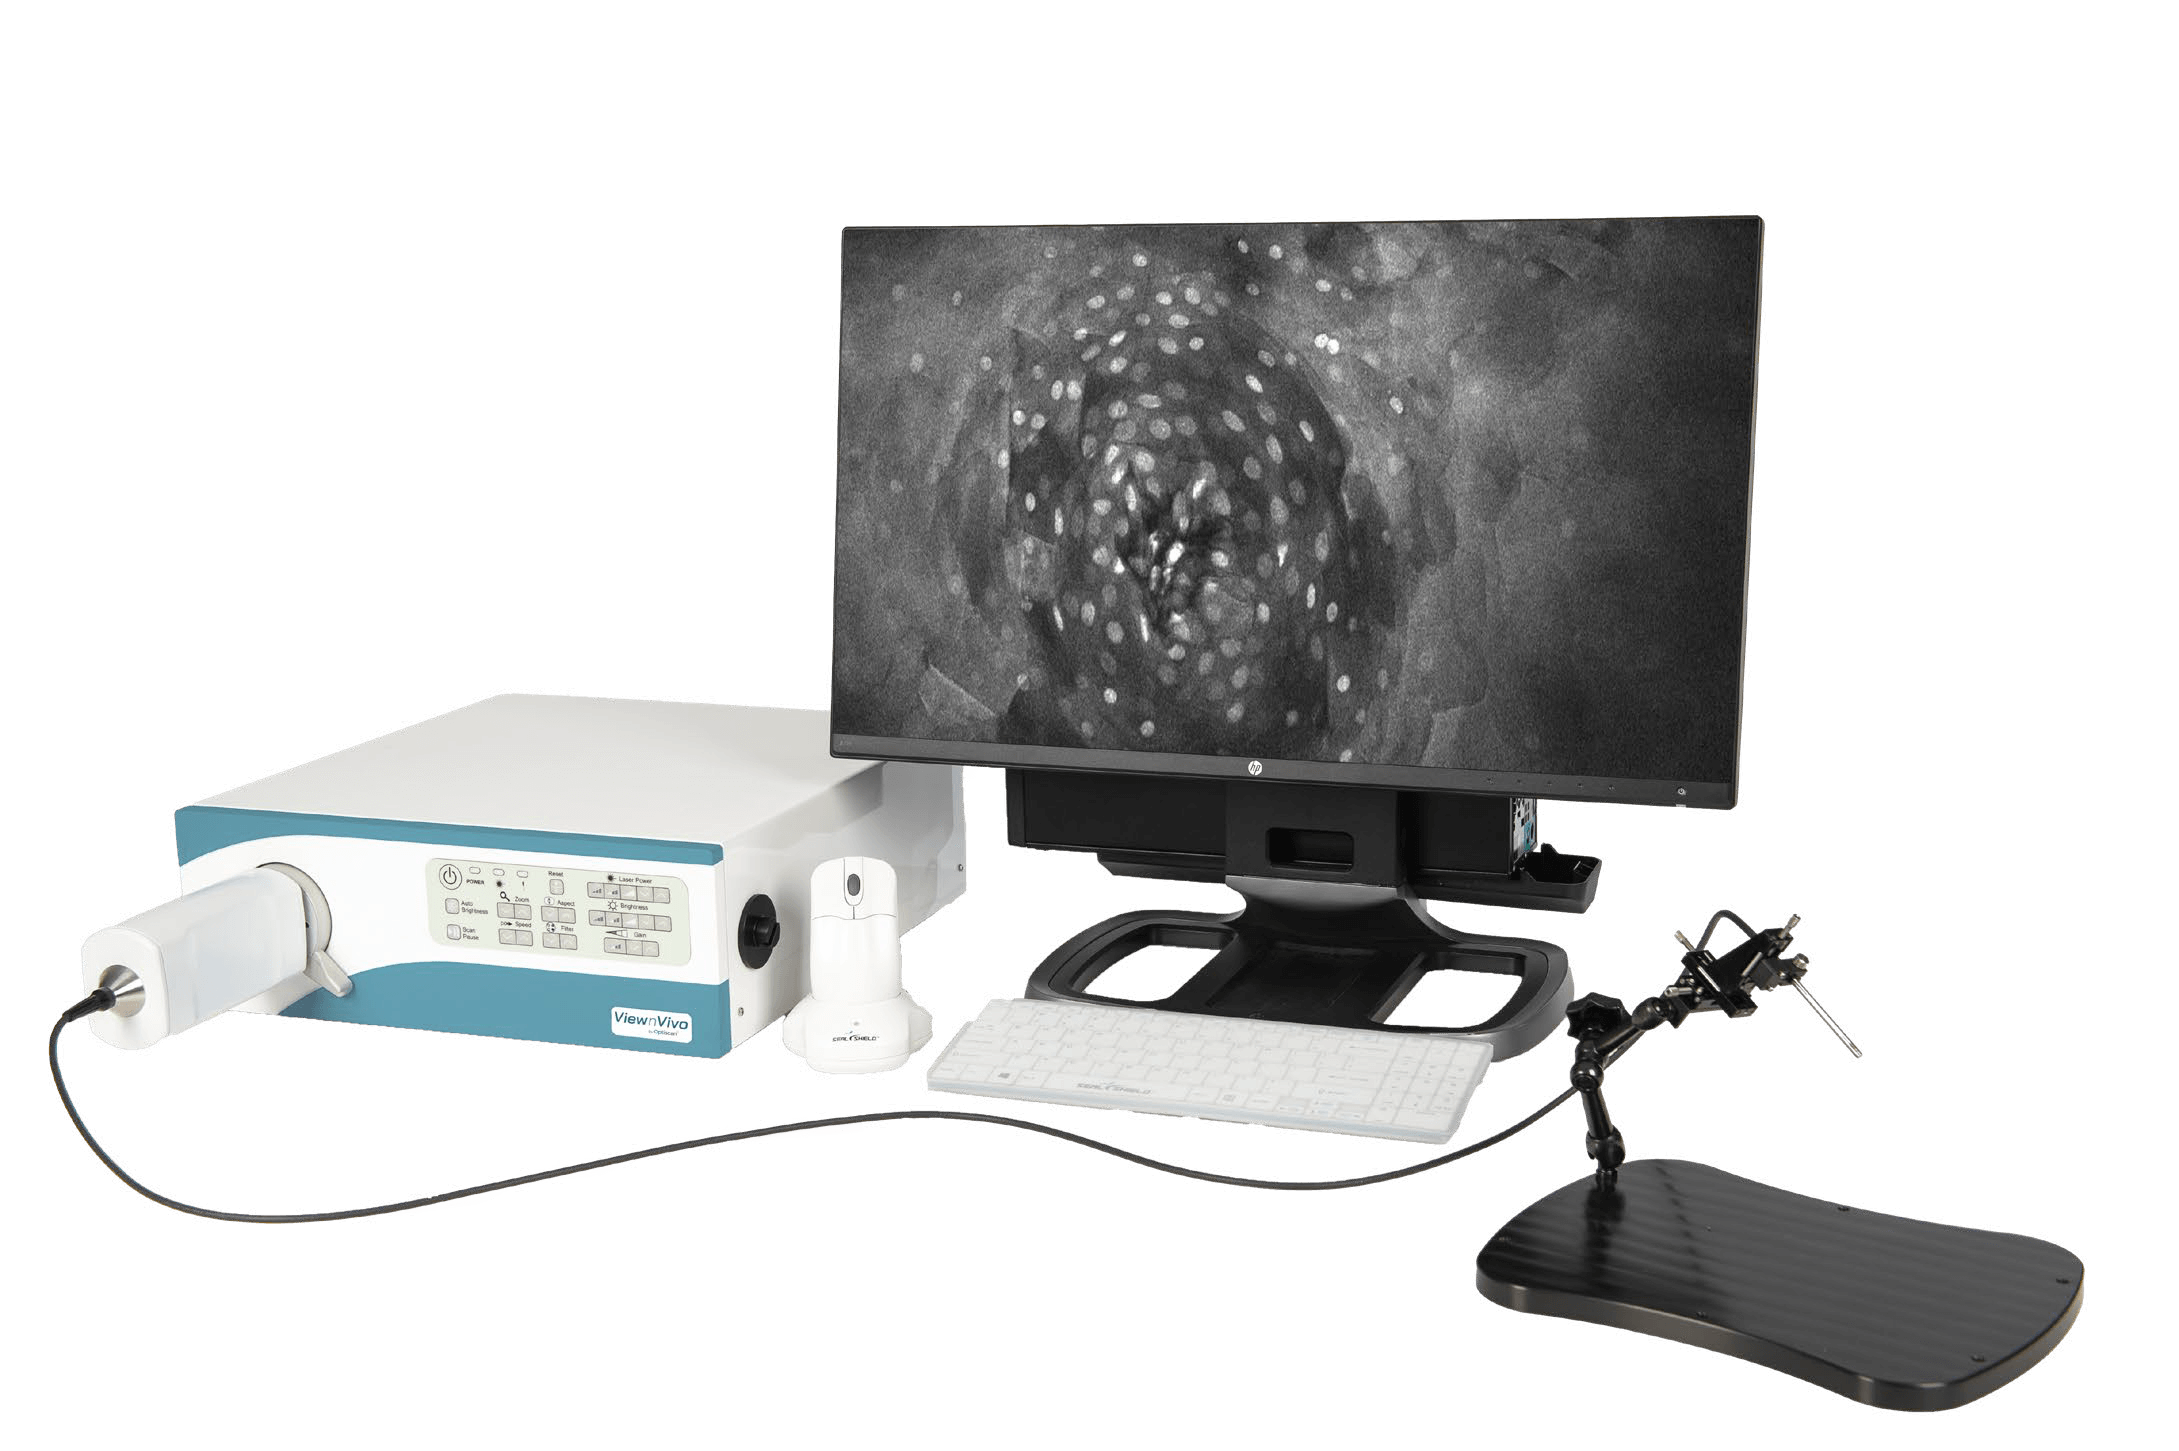

ViewnVivo® offers single-cell level live imaging, providing unique biological system insights and enabling users to see life connected. Developed with our patented confocal imaging technology, ViewnVivo® is a miniaturized in vivo imaging device that offers single-cell 3D live microscopic imaging in the palm of your hand.

Designed specifically for life sciences, pre-clinical and translational research, ViewnVivo® enables users to see systems biology in harmony, maintaining key cell structures, biological systems and cell-to-cell interactions to provide valuable translational results to accelerate drug discovery or unlock new study possibilities.